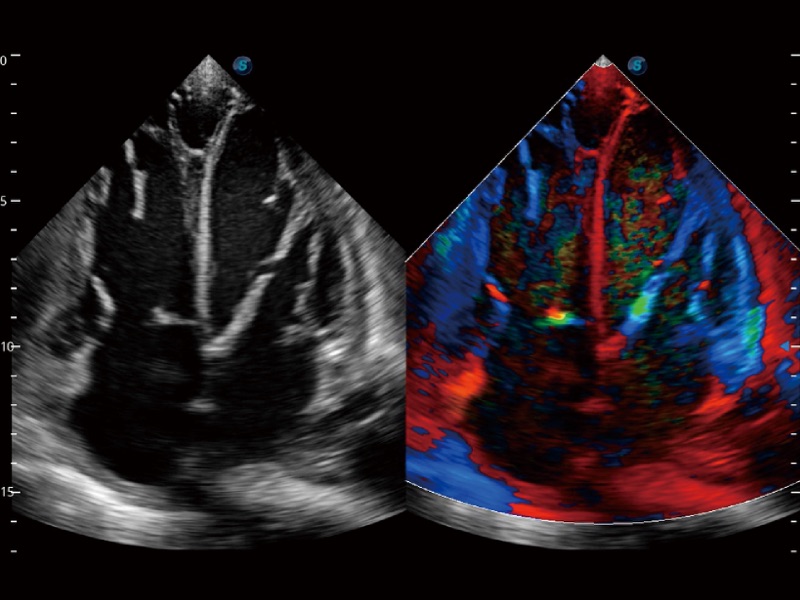

心血管应用

高分辨率血流成像技术提高了对低速血流信号的检测能力。在提高空间分辨率的同时,也克服了血流外溢现象,为用户提供更加真实的血流动力学信息。

支持运动和药物负荷协议、多心动周期存储选择,为临床观察心肌负荷状态下的室壁节段运动、评估心肌缺血状态提供更多的解决方案。

通过心肌识别技术和二维斑点追踪技术相结合,计算心肌各节段的应变应变率、速度、位移并以曲线图显示,实现整体或者局部心肌定量分析。同时可呈现牛眼图直观和准确诊断心肌的运动情况。

血管内中膜的厚度值是预测心血管疾病风险的重要指标,Auto IMT可以实现血管近场和远场内中膜厚度的自动测量,为临床提供快捷有效的诊断工具。